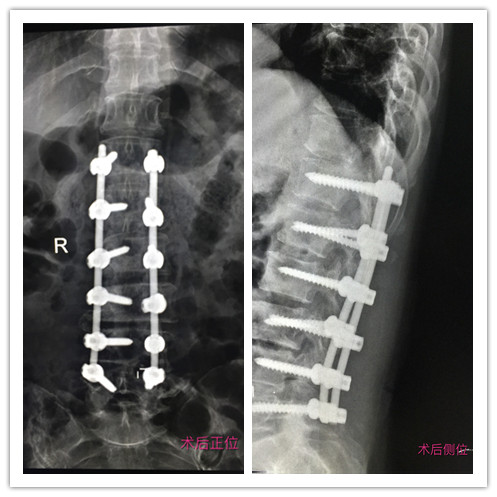

患者术前术后拍片对比

术后,患者腰腿疼痛症状明显缓解,拍片复查脊柱矫形满意,切口愈合良好,目前,患者正在康复中。

患者乔女士,62岁,胸腰椎脊柱侧弯 10余年,因腰痛、左下肢放射痛、麻木半年,间歇性跛行半年,于3月26日来我院就诊。以胸腰椎退变性脊柱侧弯,腰椎间盘突出症(L4-5),腰椎管狭窄症(L4-5)收住骨二科住院治疗。入院后及时为患者完善胸片,腰椎CT及MRI平扫等检查后,卜祥朋主任遂带领专家团队进行术前讨论,为乔女士设计手术治疗方案,并指导其行体位训练。经过精心的术前准备,3月30日,卜祥朋主任、李秀春副主任医师与齐鲁医院刘新宇教授通力合作,为乔女士实施后路椎间融合器结合后路椎弓根系统胸腰段退变性脊柱侧弯矫正术及L4-5节段椎间盘摘除、椎间植骨融合内固定术,用时5个半小时,手术顺利完成。